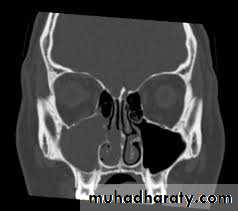

Investigations

Only the combination of diagnostic endoscopy and high-definition coronal section CT scanning will provide the maximum information. One modality is said to enhance the accuracy of the other. Furthermore, some patients with sinogenic headaches may present with an atypical history and have negative findings on examination and plain sinus radiographs. This does not rule out a sinus cause for their problem.13

Investigation

4. CT- scan of the sinuses may show

microcalcification of opaque fungal mass in the

non-invasive form due to accumulated heavy

metals, e.g. calcium, manganese. There may be

evidence of bone expansion. The invasive type,

however, will show evidence of bone destruction

with spread of disease outside the sinuses. MRI

scanning may further help delineate fungal mucin

from reactive inflammation .